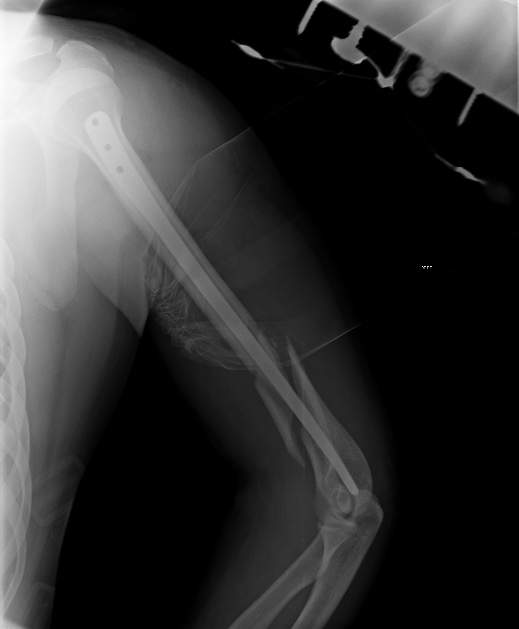

[Ortho] Псевдоартроз н/3 плеча после реЗИМО

Сейчас уже поезд ушел, но если это переделывать, основная мотивация была

бы - выстояние в проксимальном отделе.

Как-то так проксимальный отдел должен выглядеть после аналогичной операции.

Если бы выстояния не было, можно было, например, поверх стержня

наложить простенький аппарат и сдавить. С диастазом не надо было уходить

из операционной.